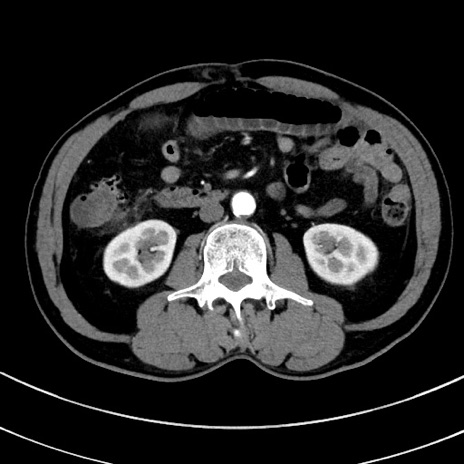

症例8(横断像)

【症例】 60歳代男性

【主訴】 黒色吐物

【現病歴】 4日前から嘔気自覚、2日前の朝食後にも嘔気あり、自分で手で嘔吐反射起こし嘔吐したところ血が混ざっていたため受診。

【既往歴】 5年前汎発性腹膜炎を伴う急性虫垂炎で手術、高血圧、前立腺肥大症、高脂血症

【身体所見】 腹部正中に手術癩痕あり 腹部平坦・軟圧痛なし膨満感あり

【データ】WBC 8400、CRP 4.54